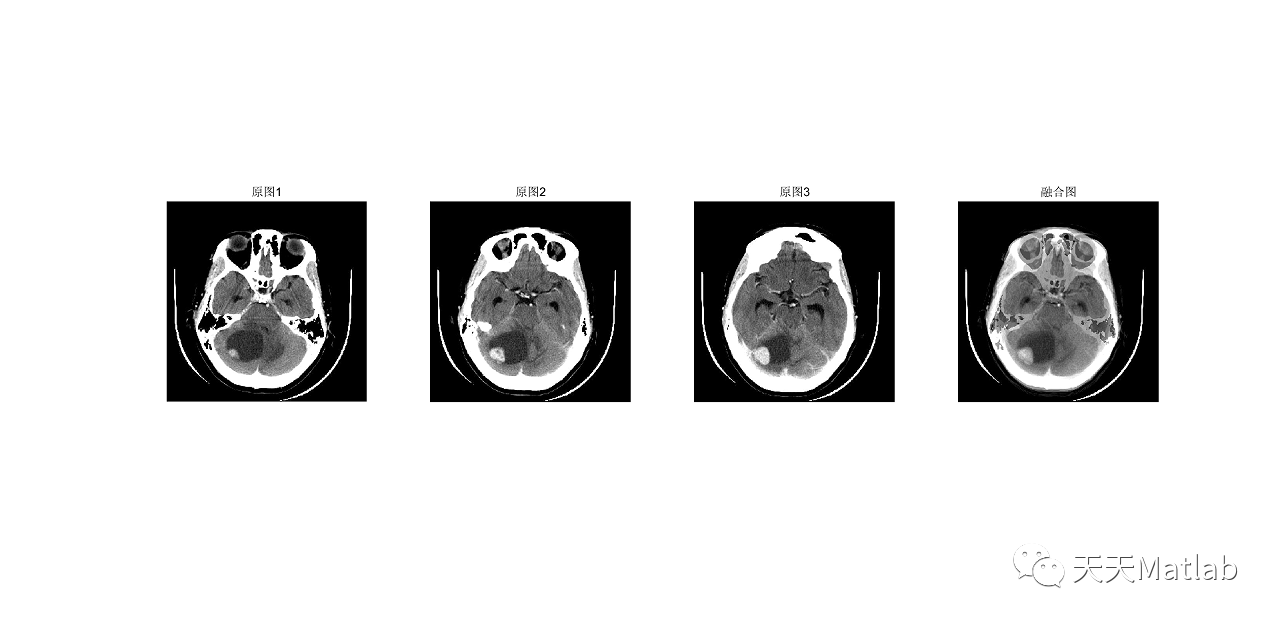

为了将低分辨率医学图像和高分辨率全色图像有效地融合,提出了主成分分析(PCA)变换和小波相结合的融合方法.小波提升后选用不同的融合规则对高低频成分进行融合,实验结果表明,该方法较好地保留了医学图像的光谱特性,提高了空间分辨率.

⛄ 运行结果

[1]邢鹏昌. 基于主成分分析变换和提升小波的图像融合[J]. 三明学院学报, 2012, 29(4):6.

PCA与小波结合的医学图像融合方法